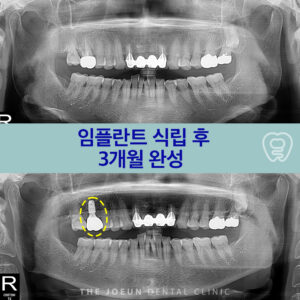

달서구치과 뼈 파괴가 심한 부위 임플란트 지연 식립

달서구치과 뼈 파괴가 심한 부위 임플란트 지연 식립   치주 질환은 성인에게 흔히 발생하는 구강 문제 중 하나로 잇몸 염증이 심해져 치아를 지탱하는 조직과 뼈까지 손상되는 질환으로 적절한 치료가 이루어지지 않으면 치아 상실로 이어질 수 있습니다. 치주 질환은 치아를 잃게 되는 가장 흔한 원인 중 하나로 잇몸이 붓고 피가 나며 더보기…